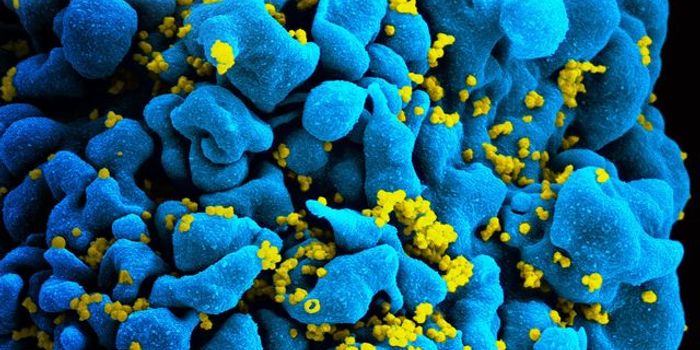

JUL 19, 2016CancerA decade-old technology to arm the immune system to fight cancer is now being adapted to fight HIV, one of the most pern ...